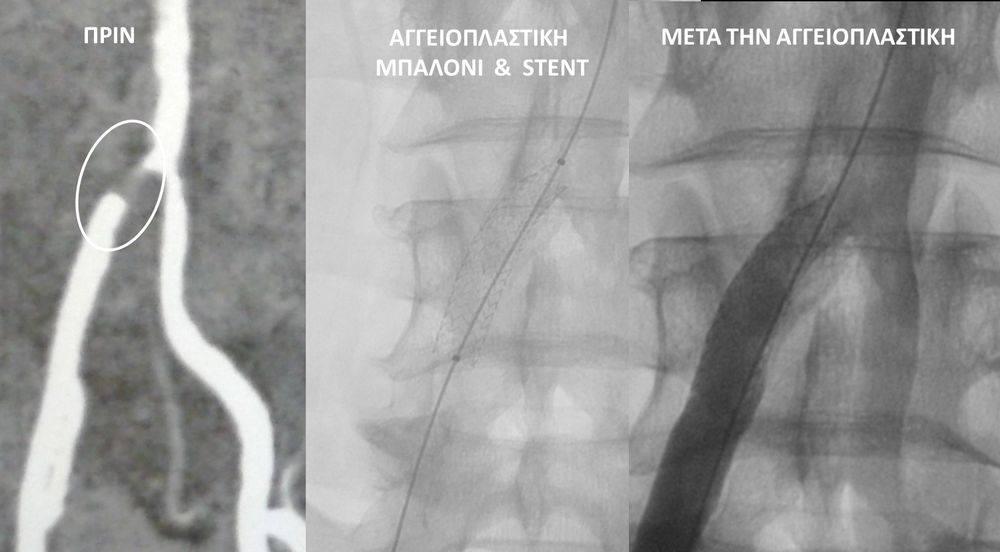

• Η αγγειοπλαστική των αρτηριών είναι μία μη χειρουργική επέμβαση που αποσκοπεί στη διάνοιξη των στενωμένων ή αποφραγμένων αρτηριών. Γίνεται με την ίδια τεχνική όπως και αγγειογραφία. Η αγγειοπλαστική των αρτηριών μπορεί να γίνει είτε με απλή διάνοιξη της αρτηρίας που εμφανίζει στένωση με μπαλόνι ή και να συνοδευθεί από τοποθέτηση ενδαγγειακής πρόθεσης (stent).